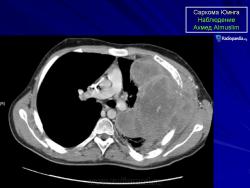

С Радиопедии.

Саркома Юинга грудной стенки.